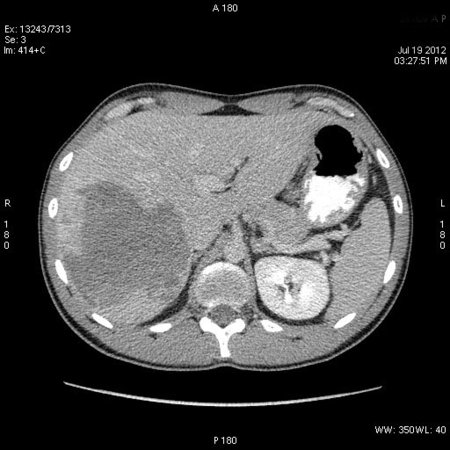

На следующий день сонографическая картина немного изменилась:

Какие мысли?

на узи на абсцесс не похоже, образование солидное ----гепатома?

Гигантская капилярная гемангиома печени.

Ангиографию надо назначить или УЗИ с контрастированием.